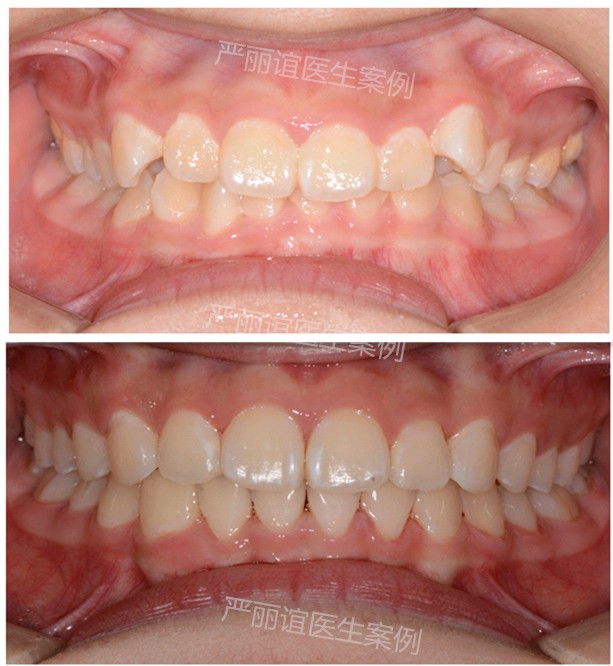

这个患者上颌两个小虎牙外凸,下颌一个畸形过大牙,自觉很影响颜值,想通过矫正改善。

检查发现她上颌最后还有一定的骨量,加上两个小虎牙外凸不是特别严重,需要2-3mm就可以排齐。下颌的畸形过大牙外面的保护层比其他牙齿厚,沟通后选择了上颌推磨牙远移,下颌片切的矫治方案。

一年半时间,矫正结束前后对比图如下。